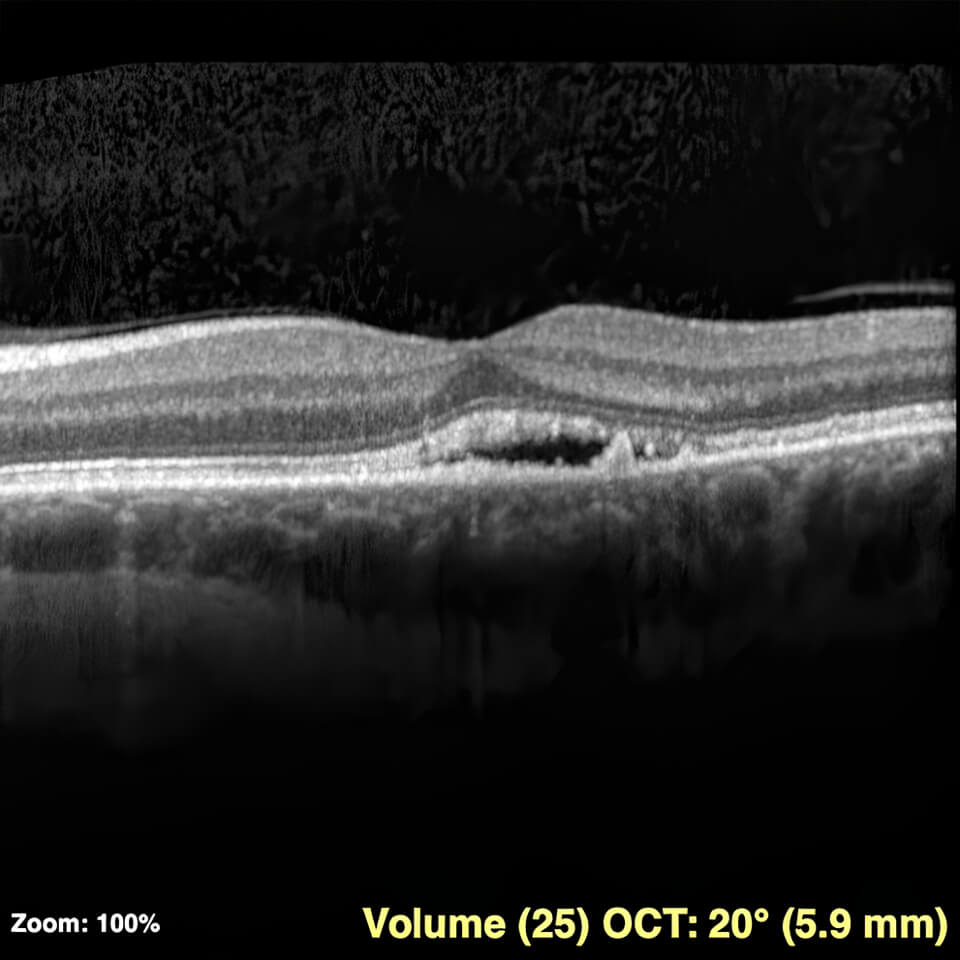

To diagnose CSR, your retina doctor will dilate your eyes and use OCT imaging to observe and quantify the fluid accumulated under the retina. Often, the doctor will order a fluorescein angiogram (an IV dye test) to determine the source of the leakage, rule out other causes of fluid, and guide treatment should it become necessary.

CSR picture upscaled